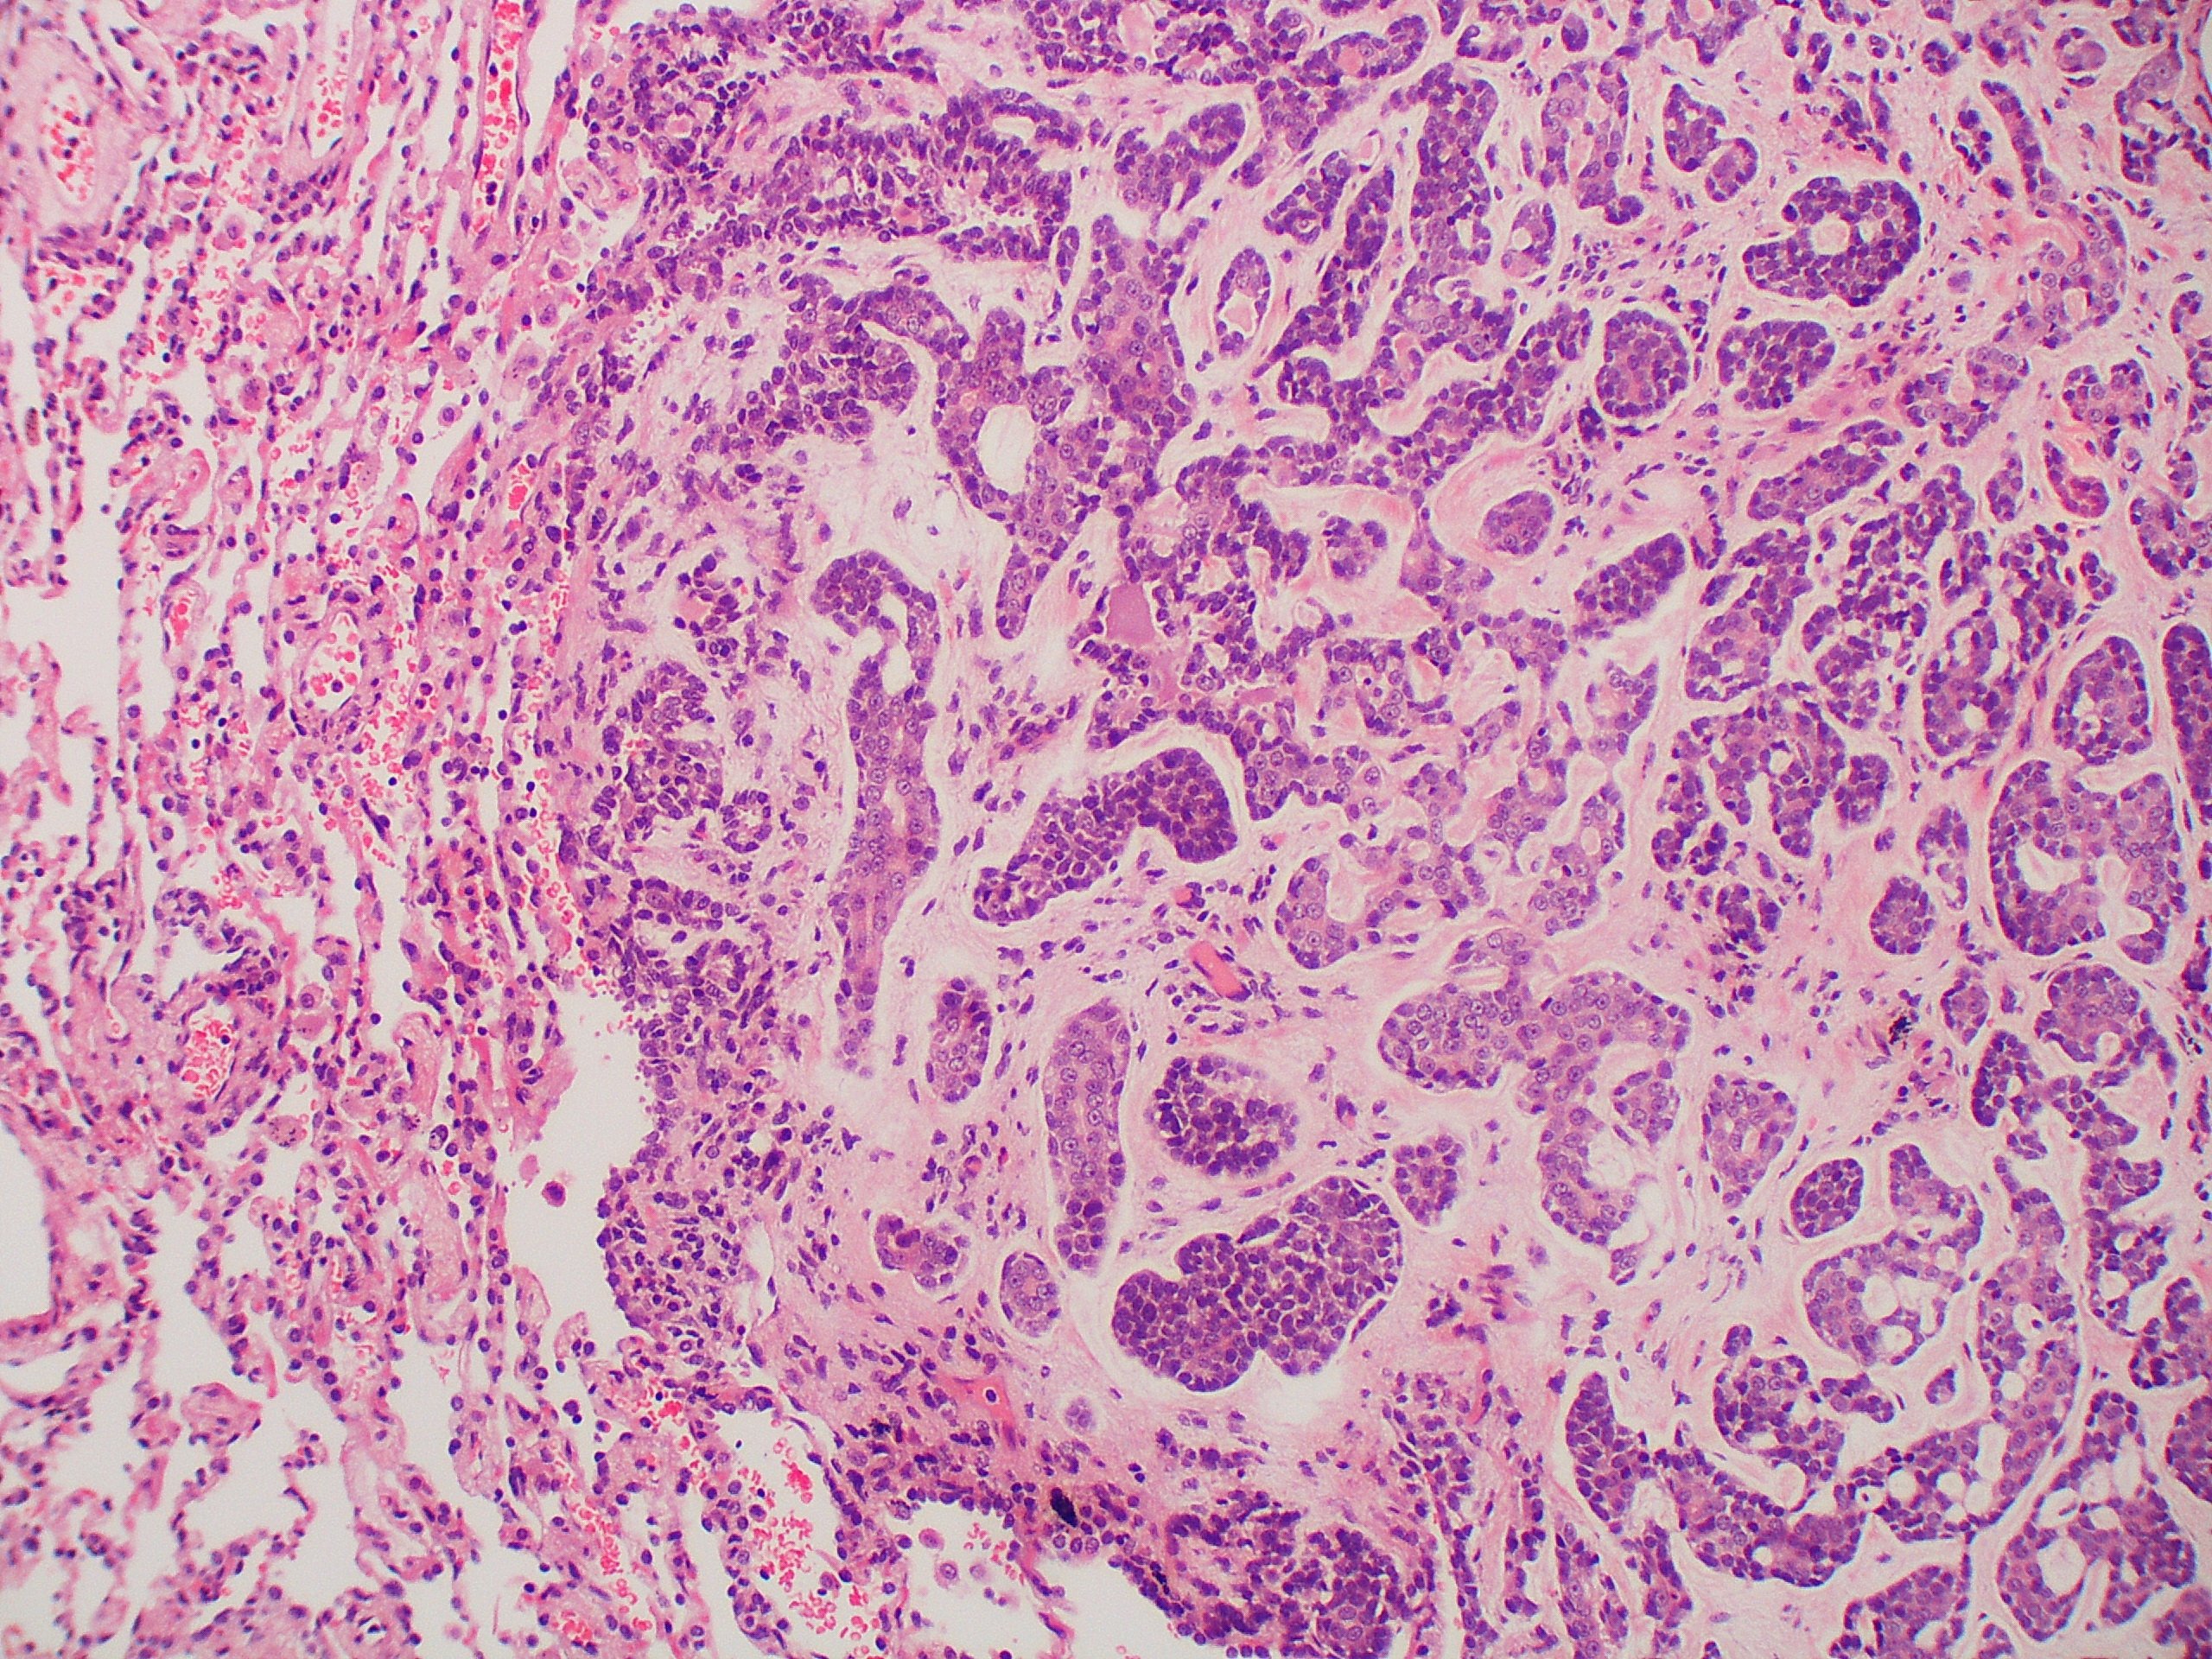

A carcinoma tumor is a malignant tumor which classically arises in the epithelial cells, the cells which line the organs and interior cavities of the body, in addition to providing the outer layer of the skin.

Carcinoma is the most common type of cancer, which includes adenocarcinoma, squamous cell carcinoma, and basal cell carcinoma. It begins in the epithelial tissue of the skin, or in the tissue that lines internal organs, such as the liver or kidneys. Carcinomas may metastasize to bone, liver, lung, brain. Carcinomas may spread to other parts of the body, or be confined to the primary location. Learn more about invasive ductal carcinoma. It is not cancer and may not become malignant. The immune system helps your body fight infections and other diseases. Squamous cell carcinoma begins in the squamous layer of the skin. Still, doctors usually recommend surgery to prevent future. There are 5 main groups. Learn more about the symptoms, diagnosis, and treatment of the common. Because bccs grow slowly, most are curable and cause minimal damage when caught and. One of the four major types of tumor, carcinoma is the most commonly seen variety in human beings, able to grow nearly anywhere in the body.